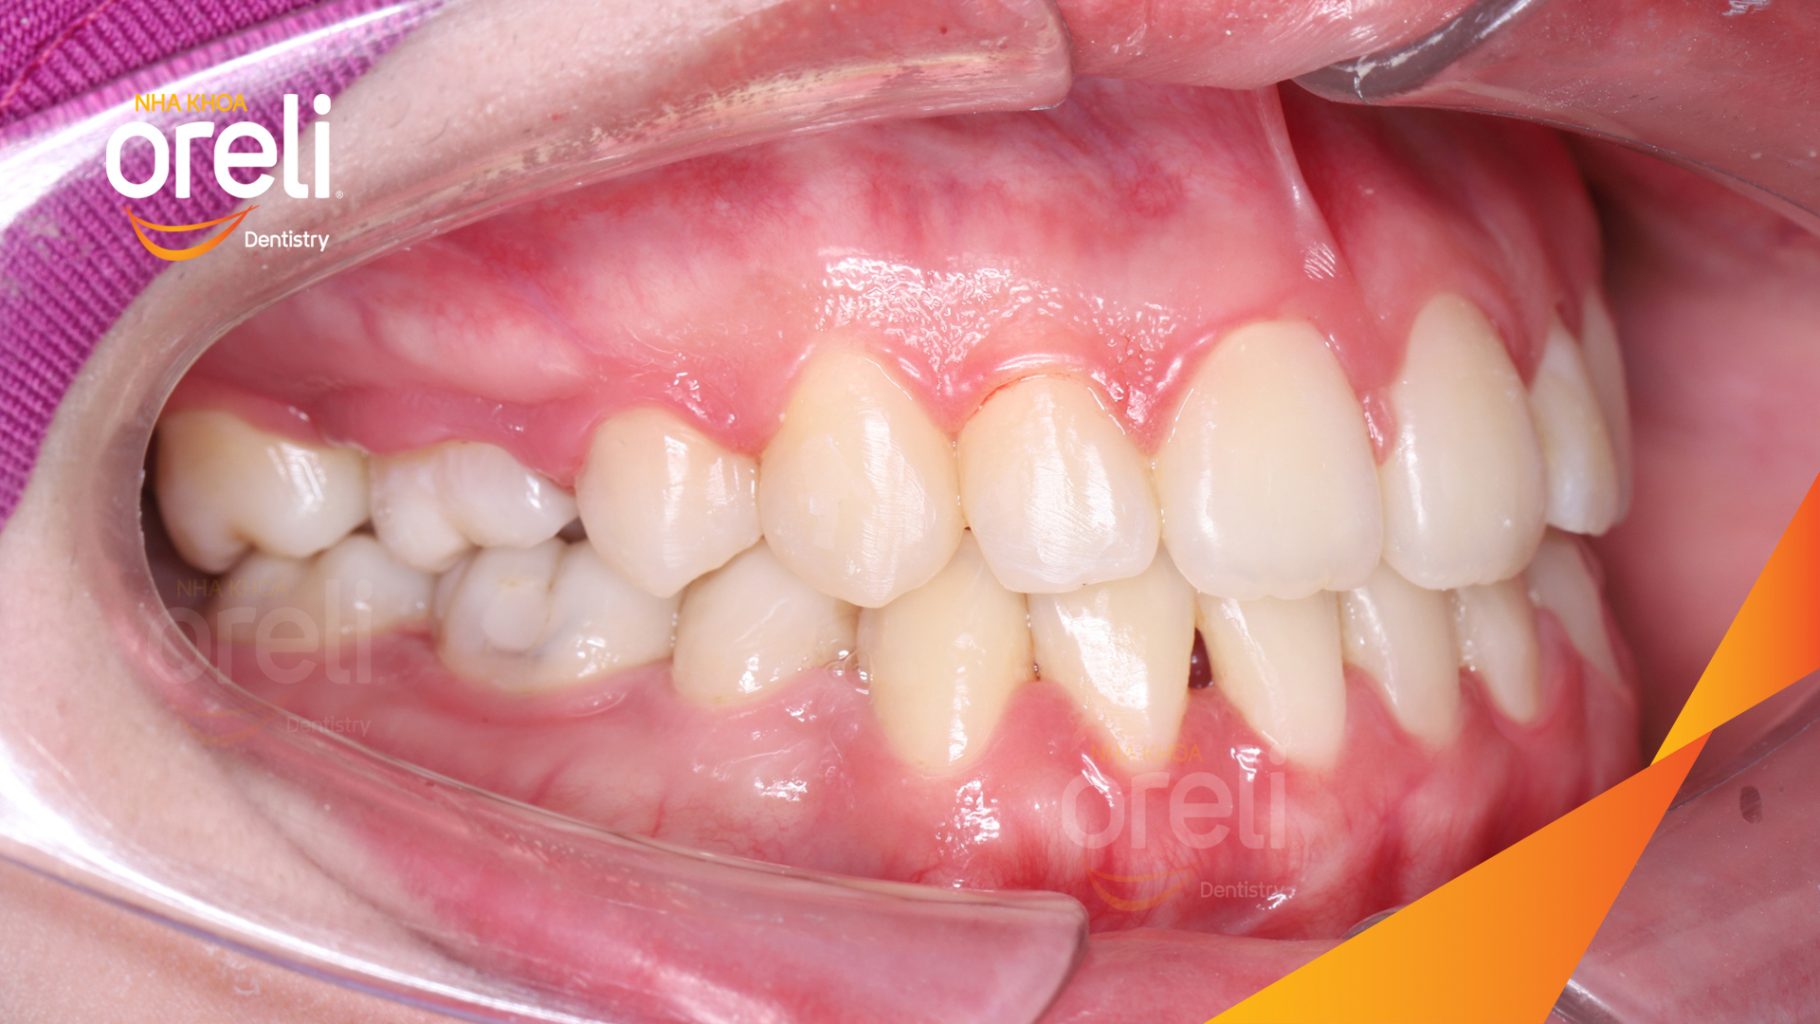

Hành trình thay đổi nụ cười ca lệch khớp cắn hạng 3, hàm dưới trượt ra trước và nhô xương hai hàm.

Hình ảnh thực tế